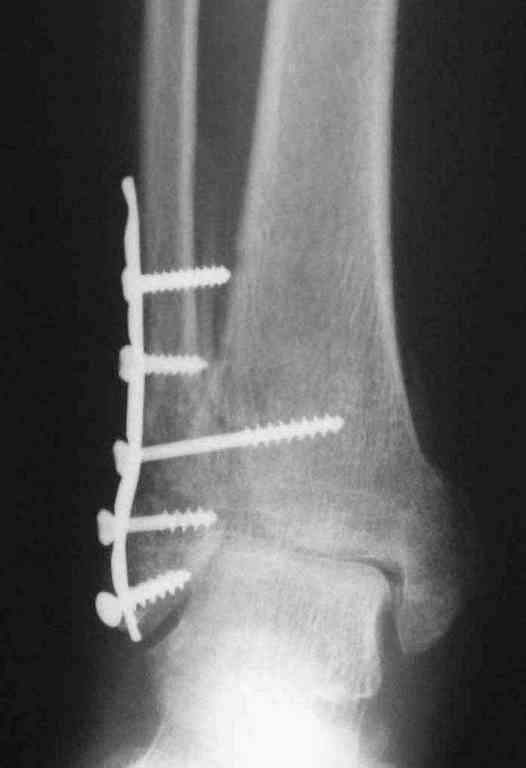

Уже 15 лет в отделении мы активно оперируем свежие переломы ГСС по принципам АО и вполне удовлетворены результатами лечения свежей травмы. В случаях же операций при позднем поступлении или реконструкции после неудачных вмешательств в ряде случаев сохраняется нестабильность ГСС, тенденция к вальгусной деформации. В свежих случаях никогда не приходилось производить шов дельтовидной связки, пластики тоже ни разу не выполнялись. Два примера на снимках.Первый - врач 38 лет, неудачно оперированный в своей больнице с двухлодыжечным переломом, разрывом МБС был повторно оперирован через 8 месяцев. Пытались восстановить длину наружной лодыжки остеотомией, освежили МБС, два месяца функционального лечения без нагрузки на стопу.Сейчас ходит с легкой хромотой, устает к обеду, вальгусное отклонение стопы корригировано супинатором. На Рграммах видны дистрофические изменения латерального эпифиза большеберцовой кости. Первый снимок через 6 месяцев после травмы, операции остеосинтеза болтом-стяжкой, удаленной по причине нестабильности и наличия свища над металлом. Второй снимок через 3 месяца после реконструктивной операции.

По снимкам в первом случае, укорочение малоберцовой приблизительно около 8-10 мм. Удовлетворительным восстановлением длины малоберцовой считается, когда на снимке суставная щель равны со всех сторон.